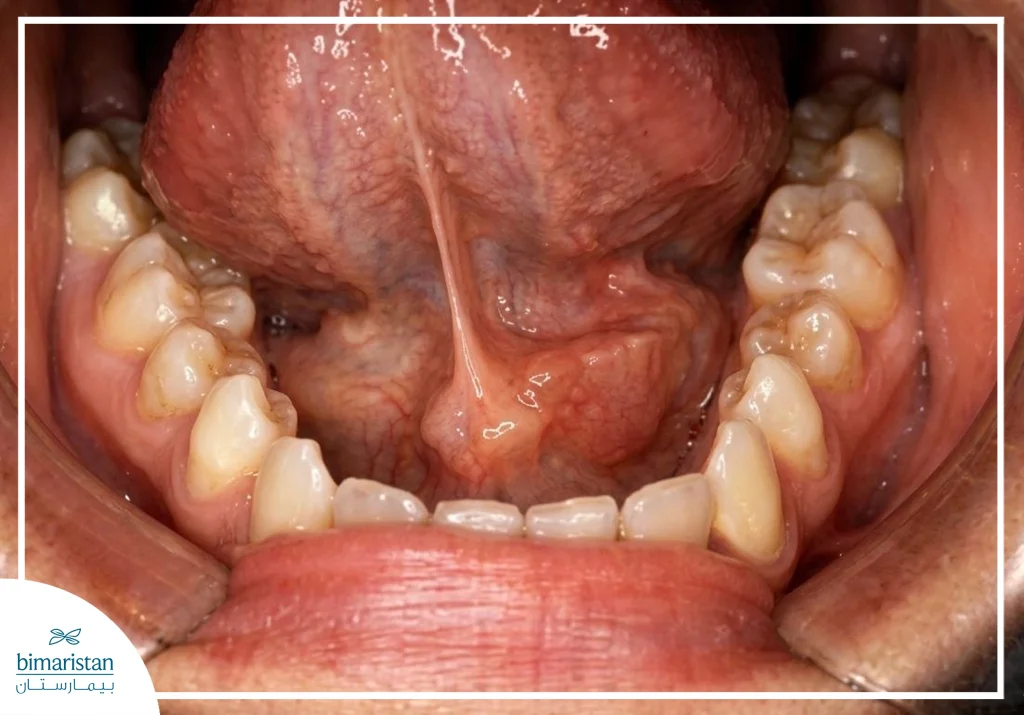

- الغدة تحت اللسان: تقع أسفل اللسان مباشرة، وتحتوي على عدة قنوات صغيرة تفرغ اللعاب في أرضية الفم.

- تقرح أو كتلة مؤلمة تحت اللسان